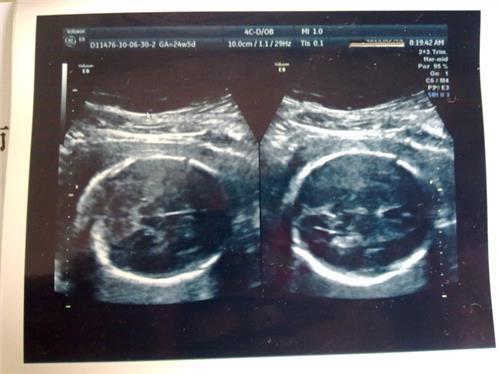

一般情况下,女性在怀孕30周的时候胎儿的双顶径的正常值在75到85毫米之间。如果双顶径的值偏小,需要遵循医生的诊疗意见做彩超检查,如果头围的测量值在正常范围内,不用过于担心,提示胎儿的头型可能是长条形或椭圆形。

如果胎儿的双颈径和头围均小于正常值,多考虑为异常情况,胎儿有小头畸形的可能。建议女性在怀孕期间密切观察胎动,多吃富含铁、钙、维生素和优质蛋白的食物。

怀孕30周的胎儿体重在1.2kg左右,双顶径的数值在7.2-8.4㎝左右,股骨长在5.3-6.2㎝左右,腹围在22.8-26.8㎝左右。